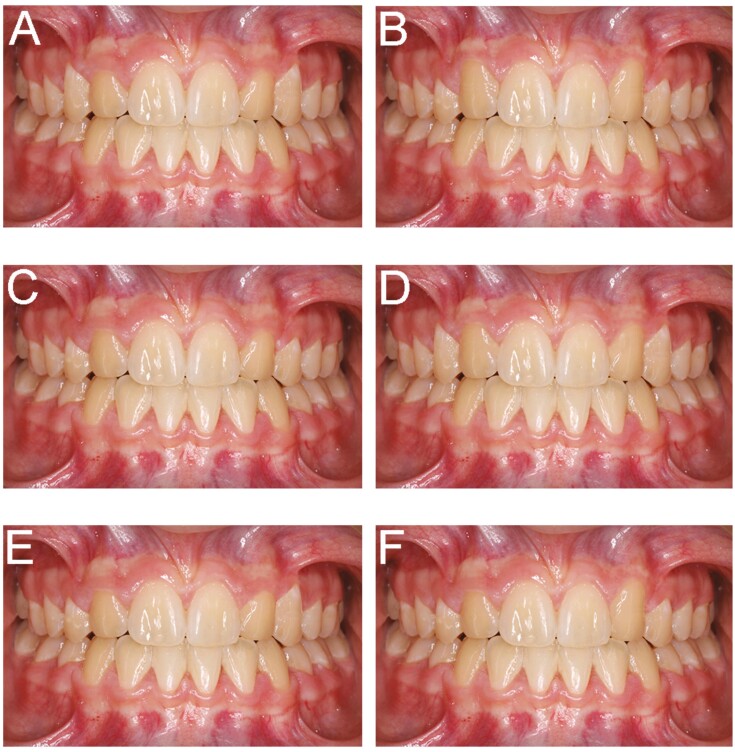

Material and methods: Images of a case treated with space closure and bilateral canine substitution were digitally modified to create gingival margin height variation for the substituted lateral incisors and canines. Six variations were created, including one conforming to accepted norms for anatomic gingival margin heights. Lay people represented by parents of orthodontic patients ranked the images based on aesthetics, with data analysed statistically using linear models at 5%.

Results: One hundred and twenty responders were included (median age 48.0 years), 50% male and 81.7% Caucasian, with 87% able to provide specific preferences. In absolute terms, the highest-ranking [image C] had substituted lateral incisor gingival margins below the central incisors (considered normal) but substituted canine margins symmetrically below the substituted lateral incisors (considered to be too low); followed by [image D] with symmetrically level gingival margins; and [image F] with asymmetric substituted lateral incisor margins and substituted canine margins symmetrically too low. The lowest-ranked [image E] had normal substituted lateral incisor margins but asymmetric substituted canine margins. Image C was most often ranked first (29.8% of responders) and image E last (22.1%). After adjusting for potential confounding effects, image E received the worse scores.

Conclusions: Anatomic norms for gingival margin height in absent maxillary lateral incisor-canine substitution do not correlate with the highest-ranking aesthetic choices of a lay population. Lateral incisor gingival margins symmetrically below the central incisors and substituted canine margins symmetrically below these ranked highest. Vertical asymmetry in the substituted canine position was considered the least aesthetic.